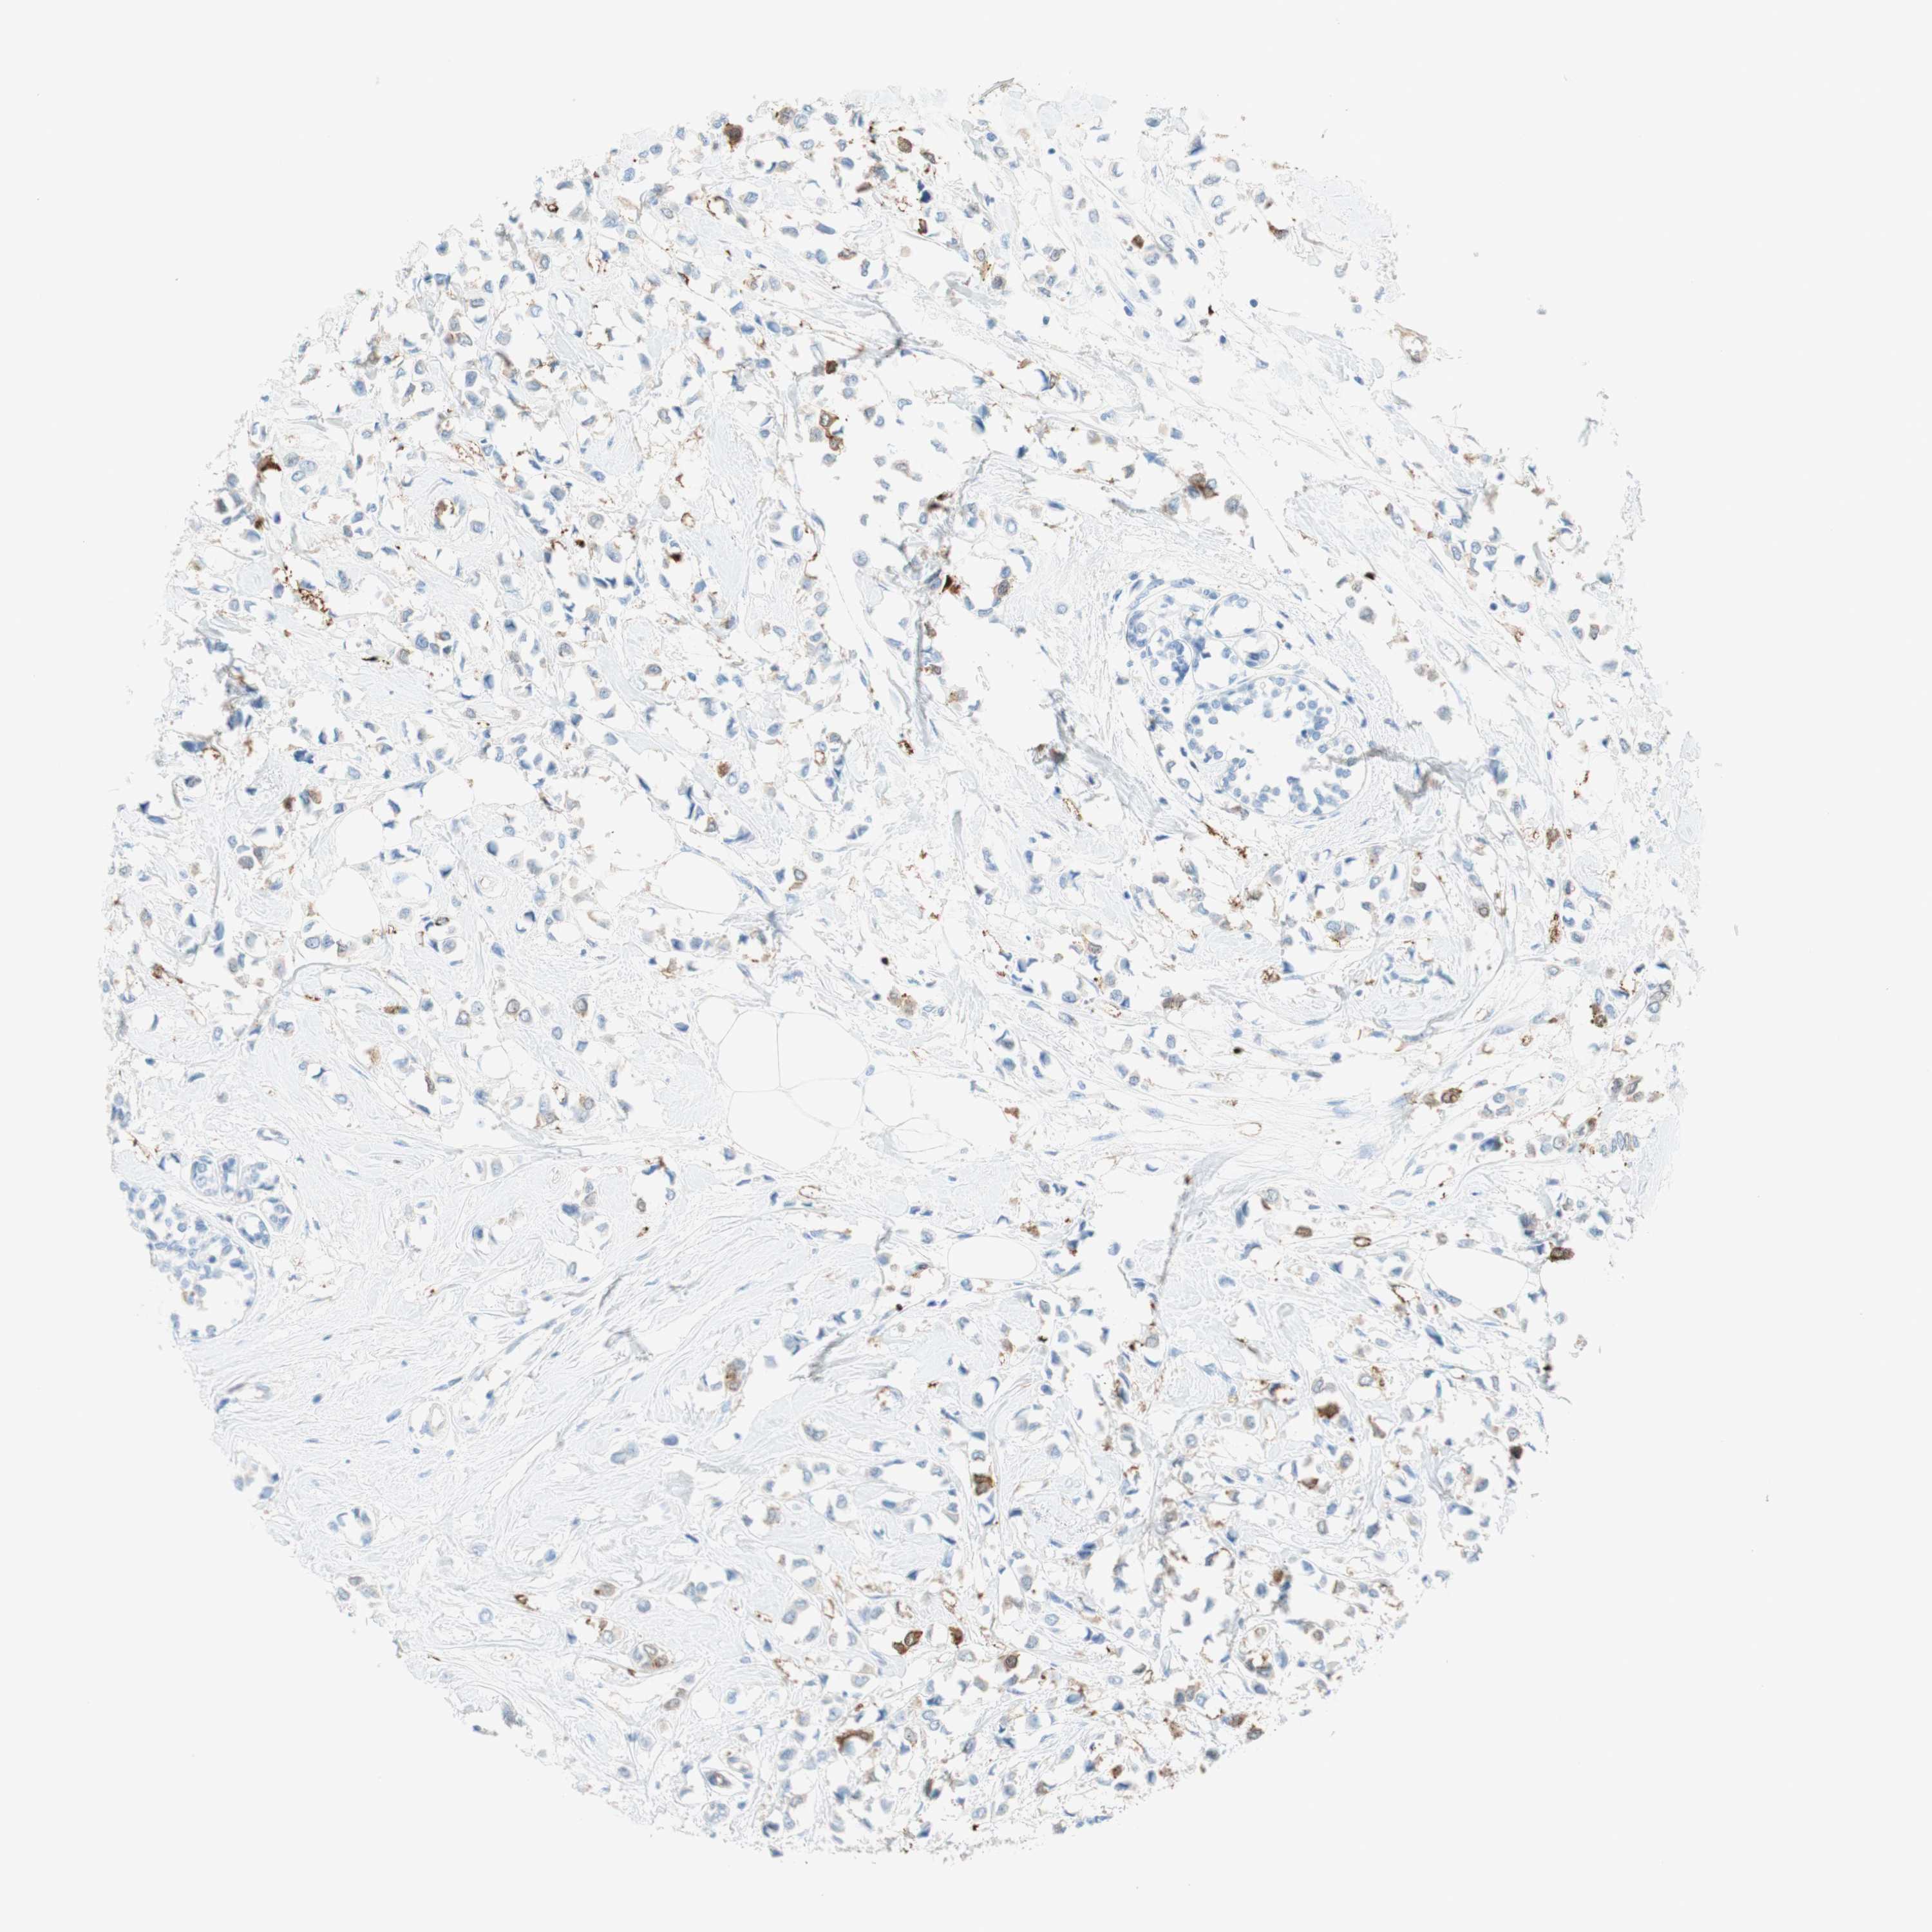

BRCA TCGA BRCA VALIDATION PROTEIN EXPRESSION

ANTIBODIES

AND

VALIDATION